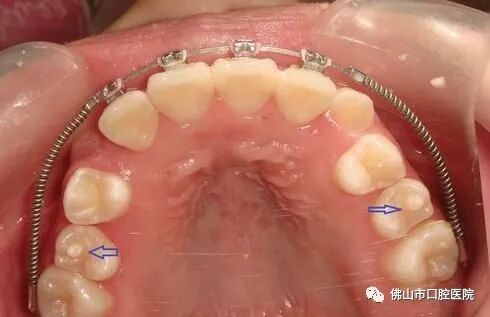

»ûÐÎÖÐÑë¼âÊÇÒ»ÖÖÏÈÌìÐÔÑÀ³Ý·¢Óý»ûÐΣ¬ÊÇÖ¸ÔÚǰĥÑÀÒ§ºÏÃæÖÐÑë»òÕßÏàÁÚµÄÑÀáÕÉÏÍ»ÆðµÄÒ»¸öÔ²×¶ÐεÄÑÀ¼â£¬Ò»°ã¸ß¶ÈÔ¼1~3mm¡£¿Éµ¥·¢»òÕß¶à·¢£¬×î³£¼ûÓÚÏÂò¢µÚ¶þǰĥÑÀ£¬³£×óÓÒ²àͬÃûÑÀ¶Ô³ÆÐÔ·¢Éú¡£